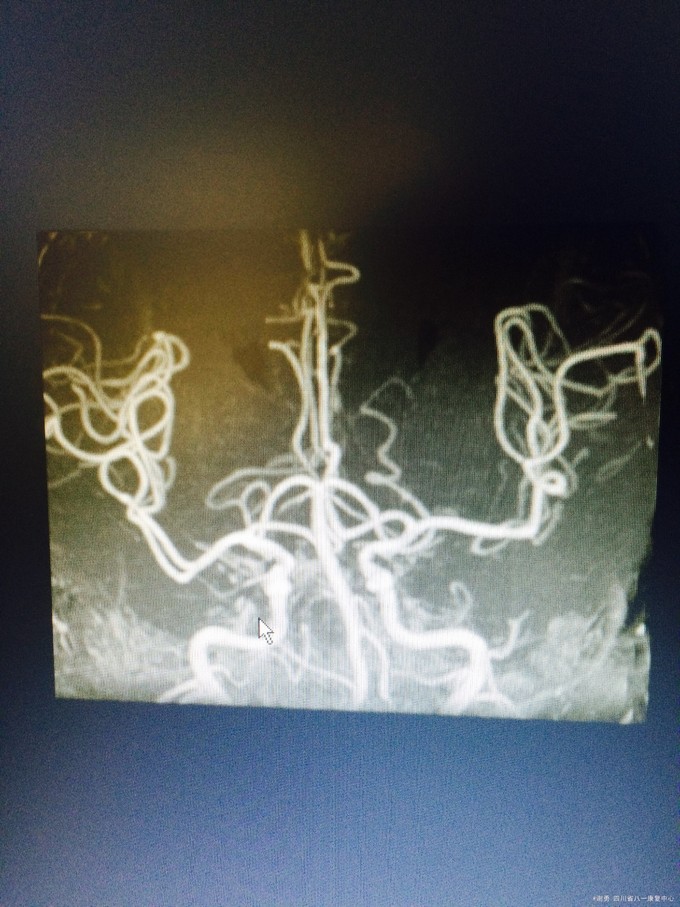

入院查体:血压165/100mmHg,扶入病房,查体合作欠佳,反应迟钝,语言缓慢,记忆力下降,定向力基本正常。四肢肌张力正常。双上肢肌力5级,下肢4级,双下肢病理征阳性;深浅感觉粗测正常。MMSE评分:18分; 辅助检查:血常规,肝肾功、血糖、电解质均正常。头颅MRI 及MRA示:双侧半卵圆中心、脑室旁,基底节区、右侧丘脑、脑干多发缺血灶改变;脑萎缩,脱髓鞘改变;双侧颈内动脉C1-4段边缘欠规则,信号欠均匀。